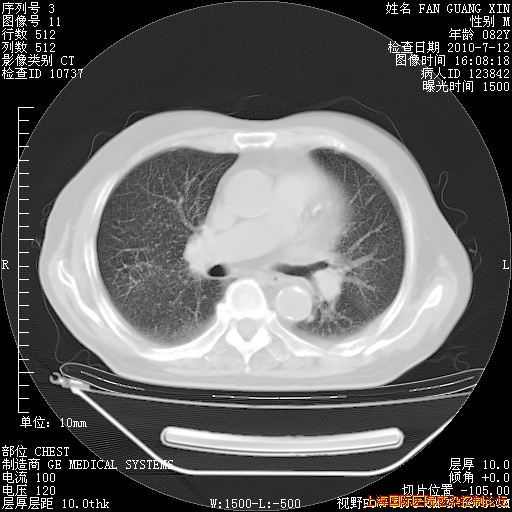

今天复查CT

今天CT

整整相隔30天的肺部CT好像有所好转啊。甲强龙减量第3天,需要观察体温。